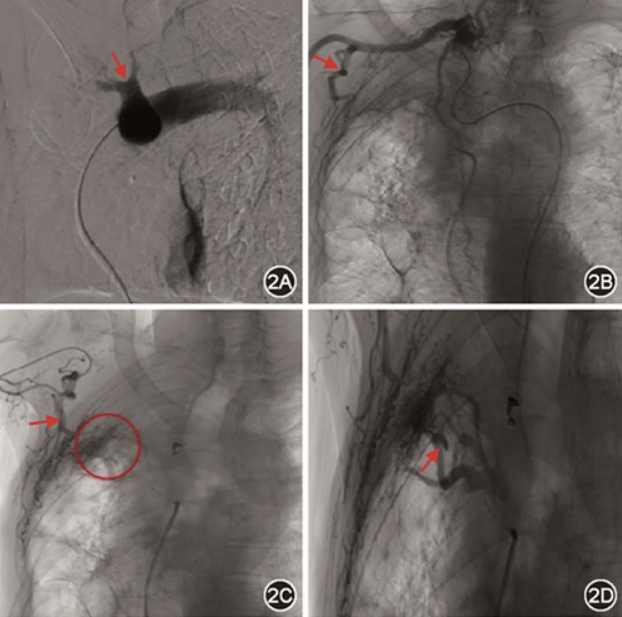

患者入院后仍有咯血,肺动静脉、支气管动脉CTA提示体动脉、肺动脉均受累,经充分评估病情后行“体动脉、肺动脉造影术+栓塞术”治疗。第一步:穿刺右侧股静脉置入8F血管鞘(TERUMO),运用5F PIG导管行双肺动脉造影,造影提示右肺动脉主干增宽,右肺动脉各肺段远端低灌注未见显影(图2A);第二步:穿刺右侧股动脉置入5 F 血管鞘,根据CTA图像,使用C3、H1、MIK、RLG、SIMMONS 2、MPA(Cook medical)等各型导管行双侧支气管动脉,双侧锁骨下动脉,双侧膈下动脉、食管固有动脉、肋间动脉造影,可见1支右侧支肋共干、2支左右共干支气管动脉、右侧第2、4、5、6、7肋间动脉,右侧胸廓内动脉、1支异位起源于右侧肋颈干的右侧支气管动脉、右侧肋颈干动脉、右侧胸上动脉、右侧胸外动脉、右侧肩胛下动脉、食管固有动脉异常,主干增粗、扭曲,末梢紊乱,并见明显体-肺动脉分流(图2B,2C),另可见右侧肺动脉A1、A3支远端呈瘤样扩张(图2D);第三步:沿股静脉入路使用MPA导管结合1.98 F微导管(Asahi)超选择性插管后右侧肺动脉A1、A3支远端瘤样扩张处,使用金属弹簧圈(Cook medical)栓塞,复造影,瘤样扩张消失;随沿股动脉入路使用300 μm聚乙烯醇颗粒(Cook medical)+500 μm明胶海绵颗粒(Varian)栓塞右侧支肋共干、左右共干支气管动脉、右侧第2、4、5、6、7肋间动脉、食管固有动脉;右侧锁骨下动脉严重扭曲,无法超选择其分支血管(包括:右侧胸廓内动脉、异位起源于右侧肋颈干的右侧支气管动脉、右侧肋颈干动脉、右侧胸上动脉、右侧胸外动脉、右侧肩胛下动脉);第四步:穿刺桡动脉,置入6 F 血管鞘(TERUMO),超选至右侧锁骨下动脉分支血管,栓塞后复造影,末梢血管消失(图3A,3B)。术中患者无明显不适,即拔管、撤鞘后,弹力绷带压迫止血,患者安全返回病房。术后患者有少许暗红色血凝块,伴发热,于术后第5天上诉症状消失。患者出院后继续口服伏立康唑200 mg(1次/12 h)抗真菌治疗。随访半年咯血未复发。

图3 栓塞后复造影,可见锁骨下动脉(图3A红色箭头)和胸外侧动脉(图3B红色箭头)迂曲增粗的末梢血管消失